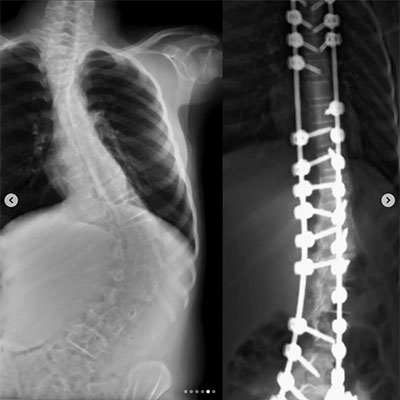

Skolyoz, omurganın yandan bakıldığında S veya C şeklinde eğrilik gösterdiği bir omurga hastalığıdır. Genellikle çocukluk ve ergenlik döneminde başlayan bu durum, omurganın düzgün hizalanmasını engeller. Skolyozun nedeni tam olarak bilinmese de, çevresel, genetik veya nöromüsküler faktörlerle ilişkili olabileceği düşünülmektedir. Hafif vakalardan ciddiye kadar değişen şiddette görülebilir ve bazı durumlarda belirti vermeden ilerleyebilir. Ancak ilerleyen vakalarda, omurga eğriliği ve eşlik eden postür bozukluğu nedeniyle fiziksel rahatsızlıklara, sırt ve bel ağrısına, solunum güçlüklerine ve organlara baskıya neden olabilir. Erken teşhis ve tedavi, skolyozun ilerlemesini engellemeye ve yaşam kalitesini artırmaya yardımcı olabilir.

Omurganın ön ve arkadan bakıldığında 8 - 10 derece üzerindeki sağ veya sol tarafa olan eğriliği ile buna eşlik eden, kendi ekseni etrafındaki dönme hareketinin (rotasyon ) oluşturduğu bir şekil bozukluğudur. Skolyoz omurga deformiteleri içerisinde en sık karşılaştığımız ve ilerleyen evrelerde ciddi duruş bozukluklarına neden olan üç boyutlu bir omurga deformitesidir.